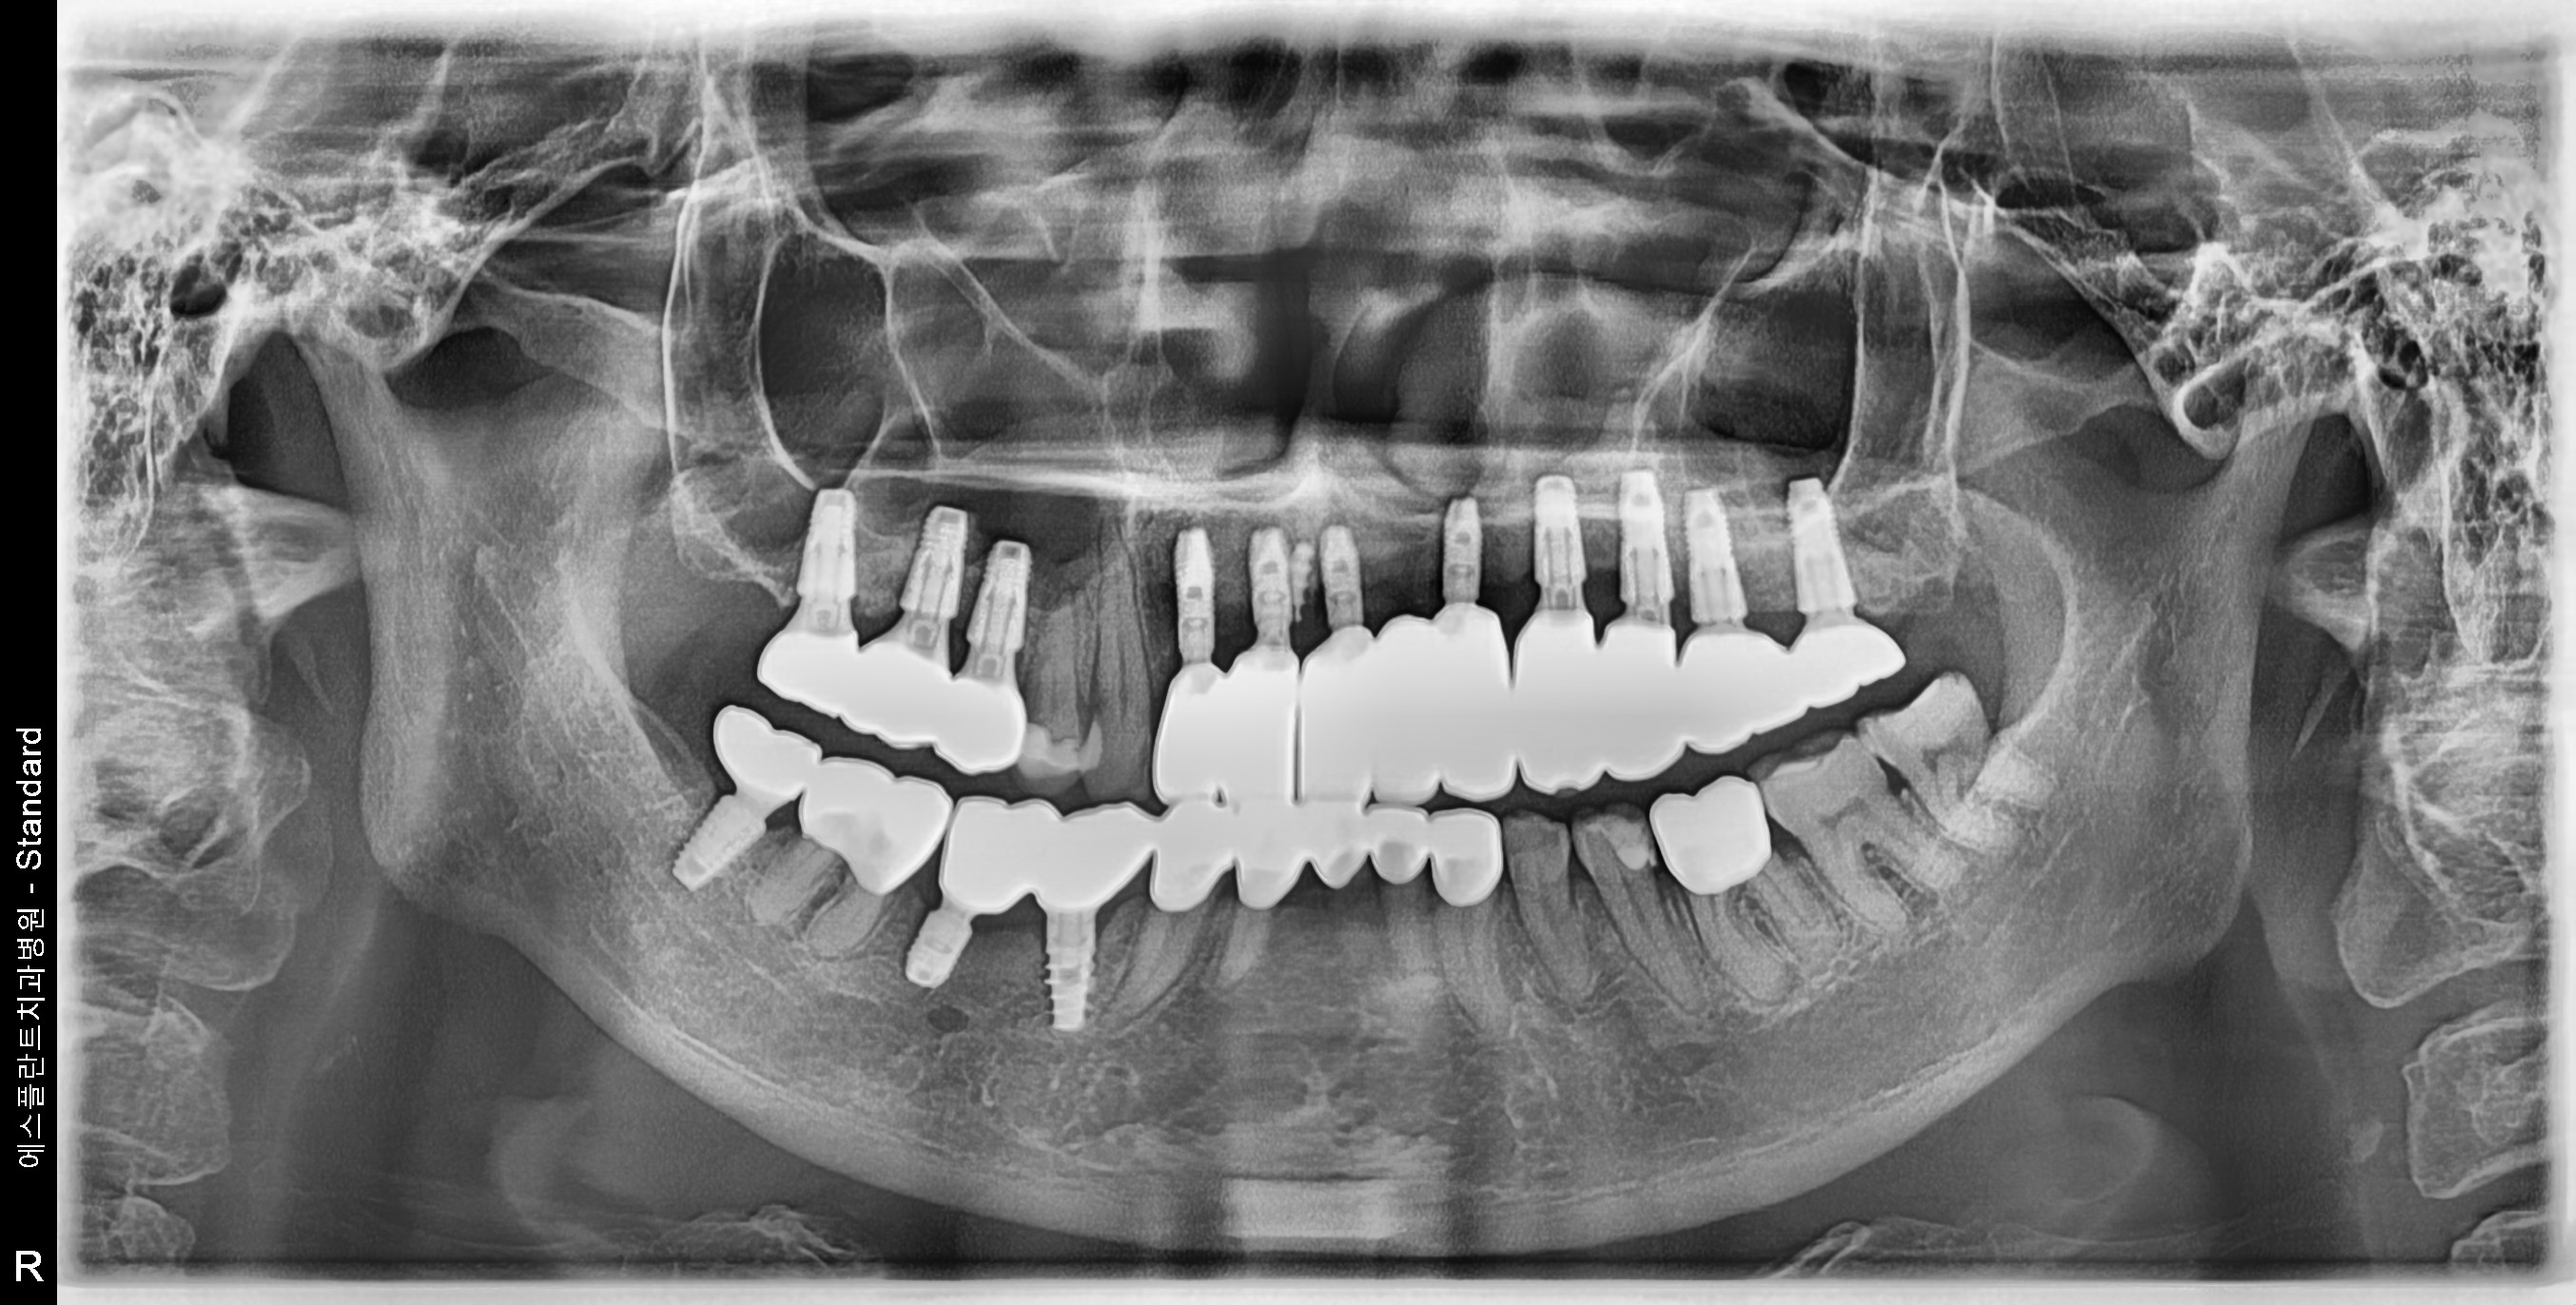

Old Detal Implant removing, Dental implant, Sinus-lifting, Bone graft

63 y.o, Kazakhstan

Operating dentist:Roh Hyun Ki